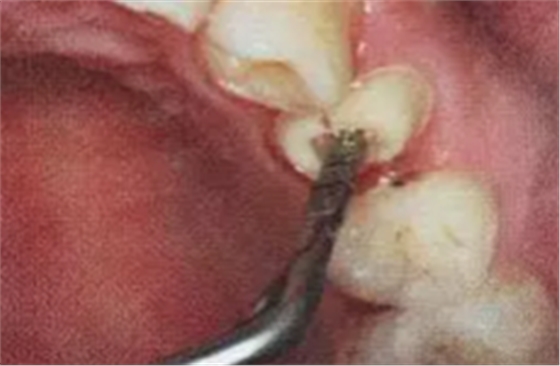

2. 清除根管壁殘留物

根管壁殘留物的存在直接影響纖維樁的粘接和固位,這也是導(dǎo)致纖維樁脫落的主要原因。

(根管內(nèi)殘留物)

個(gè)人見解:必要的情況下先開闊根管口建立一定的視角后,慢速手機(jī)上G鉆為引導(dǎo)鉆,由號遞增引導(dǎo)開闊通路;P鉆預(yù)備樁道,同樣需要由小向大號遞增,直到選擇好適合的號預(yù)備到規(guī)定測量的深度即可,再配合纖維樁系統(tǒng)中各型號纖維樁所匹配的樁道鉆,預(yù)備、修整成與纖維樁相適應(yīng)的樁道。

預(yù)備后根管壁上會(huì)不同程度的牙膠和封閉劑等殘留物,所以樁道預(yù)備前后建議X線片輔助檢查預(yù)備深度等情況,而殘留物也會(huì)很清晰地顯現(xiàn)。

根管銼去除殘留物,很難去除干凈,而備取樁道時(shí),禁止使用牙膠溶解劑(如:丁克除、氯仿)等有機(jī)溶劑去除殘留物,以防破壞根尖區(qū)牙膠的封閉和防止附著根管壁影響粘接。

(超聲去除根管殘留物)

通常此時(shí)以超聲潔牙機(jī)更換較細(xì)工作尖進(jìn)入根管(根管消毒沖洗液配合清潔工作后面會(huì)提到),徹底去除樁道根管壁上的附著殘留物,效果明顯。再配合X線片、根管顯微鏡輔助檢查清理的情況下更佳。